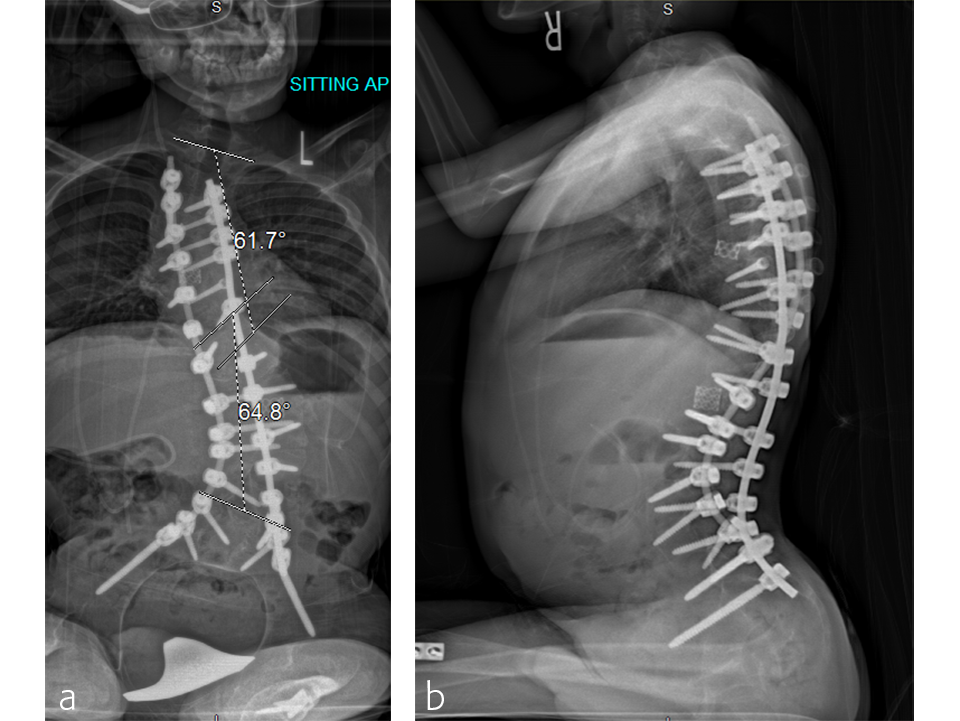

A T2 to pelvis, two-level vertebral column resection (VCR) was completed at the McGill University Health Center in 7 hours (Figs 5–7).